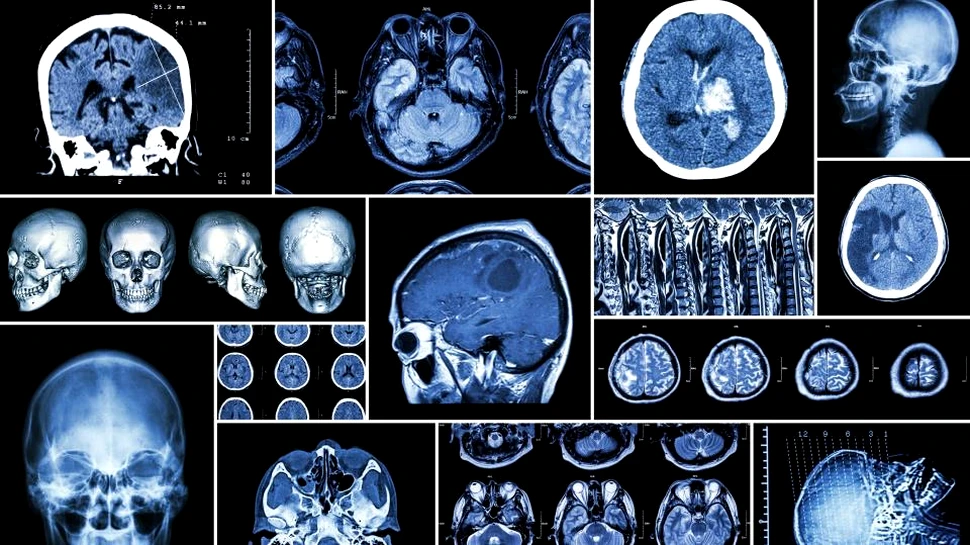

Savanţii de la Karolinska Institutet din Suedia au creat o hartă sistematică şi detaliată a tipurilor de celule a sistemului nervos la şoareci. Harta, care poate oferi noi indicii despre originea diverselor boli neurologice, este prezentată în jurnalul Cell. Pe viitor, cercetătorii vor folosi aceleaşi metode pentru a carta creierul uman la un nivel similar de detaliat.

Deşi există multe tipuri de celule, iar specialiştii au suficiente informaţii despre acestea, nu există un atlas sistematic care ar permite acestora să vadă imaginea de ansamblu a sistemului nervos şi relaţiile (deseori complexe) dintre varii tipuri de celule ale sistemului nervos la mamifere.

Cunoaşterea aceasta a diferitelor tipuri de celule ale creierului poate fi folosită pentru înţelegerea originii unor boli. Circa o treime din bolile neurologice apar în timpul dezvoltării embrionare. În ultimii 15 ani, un număr însemnat de studii genetice au identificat genele care contribuie la boli precum schizofrenie, scleroză multiplă, autism, Alzheimer şi Parkinson. Totuşi, bolile provin de la un anumit tip de celule, într-o anumită regiune şi la un anumit timp, depinzând de locul şi momentul activării genelor relevante.